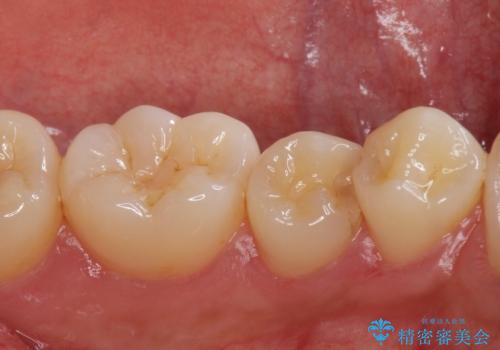

- 矯正前の患者様です。検査により虫歯がありましたのでe-maxインレー治療を行いました。

- e-maxインレー 7.7万×2費用は治療当時の料金となります